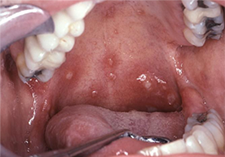

Aphthous Ulcers (a.k.a aphthous stomatitis, canker sores)

Presentation

Signs

Based on the clinical examination and on the patient’s medical history, a diagnosis of aphthous ulcers is determined.